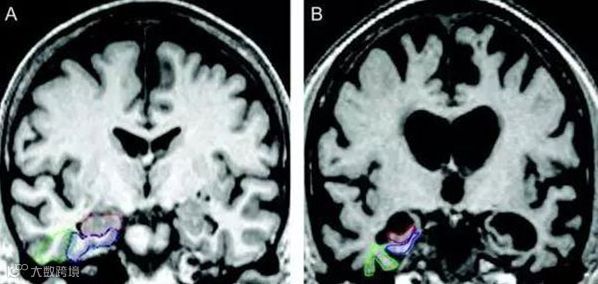

阿尔兹海默症发病是缘由脑内β-淀粉样蛋白和Tau蛋白出现异常的结果,

这两种蛋白都是阿尔兹海默症的标志性蛋白,他们在人脑内共同作用,

其中,β-淀粉样蛋白,是阿尔茨海默病患者认知能力下降和记忆力减退的重要源头。

于是乎,必须出现一种药物彻底根治β-淀粉样蛋白和Tau蛋白在人脑中的破坏,

所以目标已经很明确了,找到β-淀粉样蛋白并KO它,